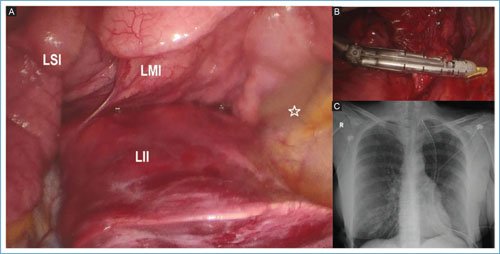

Debido a la función pulmonar limítrofe, se programó para segmentectomía de lóbulo inferior izquierdo. En cirugía se evidenció pulmón izquierdo con presencia de tres lóbulos; superior, medio e inferior (Fig. 2A). Se realizó lobectomía inferior izquierda con manejo vascular y bronquial individual a nivel hiliar (Fig. 2B). Se colocó un drenaje pleural acanalado 24 Fr.

Figura 2. A: foto quirúrgica que demuestra cisura mayor y menor dividiendo pulmón izquierdo en lóbulo superior izquierdo (LSI), lóbulo medio izquierdo (LMI) y lóbulo inferior izquierdo (LII). La estrella marca la pared posterior del hemitórax izquierdo. B: manejo vascular de la arteria de lóbulo inferior izquierdo. C: radiografía de tórax en proyección posteroanterior del posquirúrgico inmediato con adecuada expansión pulmonar.

La paciente evolucionó favorablemente con retiro del drenaje pleural a los tres días del posquirúrgico (Fig. 2C) y egreso hospitalario a los cinco días.